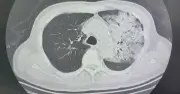

Một bệnh nhân 70 tuổi tại Trung Quốc bị viêm phổi nặng do vi khuẩn Legionella, nghi ngờ từ điều hòa lâu ngày không vệ sinh. Bệnh tiến triển nhanh, tỷ lệ tử vong cao, cần cảnh giác triệu chứng dễ nhầm với cảm cúm.